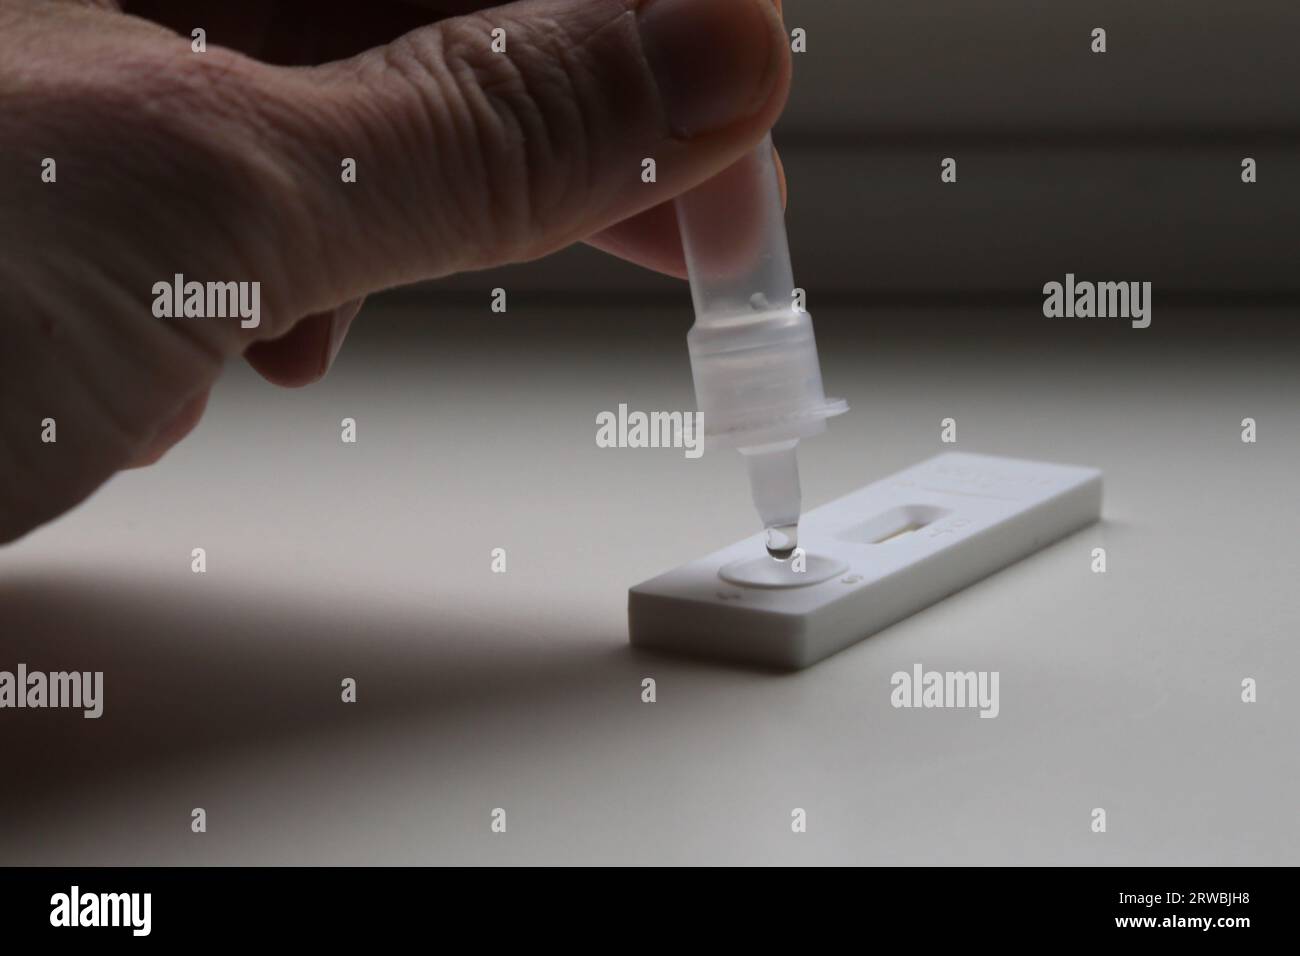

A medical, home covid test using antigen technology to check coronavirus antibody and keep people safe. Express health testing for covid 19 virus Stock Photohttps://www.alamy.com/image-license-details/?v=1https://www.alamy.com/a-medical-home-covid-test-using-antigen-technology-to-check-coronavirus-antibody-and-keep-people-safe-express-health-testing-for-covid-19-virus-image484480047.html

A medical, home covid test using antigen technology to check coronavirus antibody and keep people safe. Express health testing for covid 19 virus Stock Photohttps://www.alamy.com/image-license-details/?v=1https://www.alamy.com/a-medical-home-covid-test-using-antigen-technology-to-check-coronavirus-antibody-and-keep-people-safe-express-health-testing-for-covid-19-virus-image484480047.htmlRF2K45Y6R–A medical, home covid test using antigen technology to check coronavirus antibody and keep people safe. Express health testing for covid 19 virus

Corona antigen Rapid Test Kit, Self-test Stock Photohttps://www.alamy.com/image-license-details/?v=1https://www.alamy.com/corona-antigen-rapid-test-kit-self-test-image566354241.html

Corona antigen Rapid Test Kit, Self-test Stock Photohttps://www.alamy.com/image-license-details/?v=1https://www.alamy.com/corona-antigen-rapid-test-kit-self-test-image566354241.htmlRM2RWBJH5–Corona antigen Rapid Test Kit, Self-test